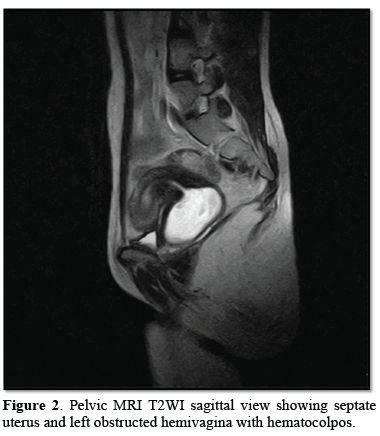

18 year’s old unmarried female was admitted in our casualty with complaints of acute abdomen. Acute onset in pain which was moderate in intensity, continuous without any relieving or aggravating factors mainly localized in the lower abdomen and associated with vomiting. Her previous menstrual cycle was 3-4/28-30 days with complaints of dysmenorrhea and LMP was two weeks back. She was stable and there was no pallor. Her pulse was 84 bpm, BP- 110/80 mmHg, RR- 20/min. On examination, there was slight tenderness and an ill-defined mass felt in left iliac fossa with rebound tenderness. On speculum examination, cervix was flushed with vagina; bulge is seen right vaginal wall. A cystic non-tender mass felt in right fornix with restricted mobility projecting in vagina on bimanual examination. So, possibility of appendicular lump or left TO mass was kept. Blood investigations were normal. Urine pregnancy test (UPT) was negative. Transabdominal ultrasonography showed septated uterus, cervix and vagina with non-visualization of left kidney. A cystic mass showing internal echoes on the left side of vagina and a septate uterus with blood in the cavity was noted. On MRI abdomen and pelvis, a complete septate uterus with haematocolpus of left hemivagina with absent left kidney and solitary right kidney showing hypertrophy was noted i.e., OHVIRA syndrome (Figures 1-3).